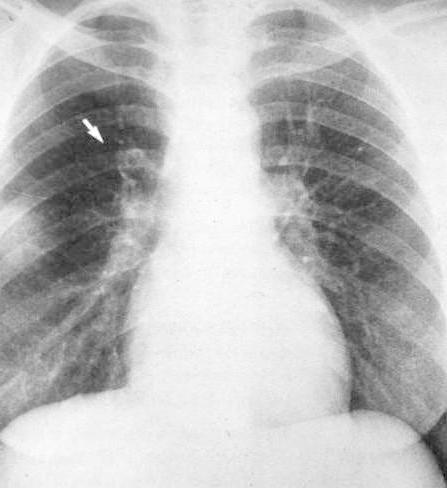

Pneumonia

The "Silhouette"

Sign = Indistinct Heart Border

Location: Middle lobe or Lingula

Example: Pneumonic infiltrate in upper segment of middle lobe (r) visible as

indistinct heart border in frontal projection

and clearly visible in lateral projection